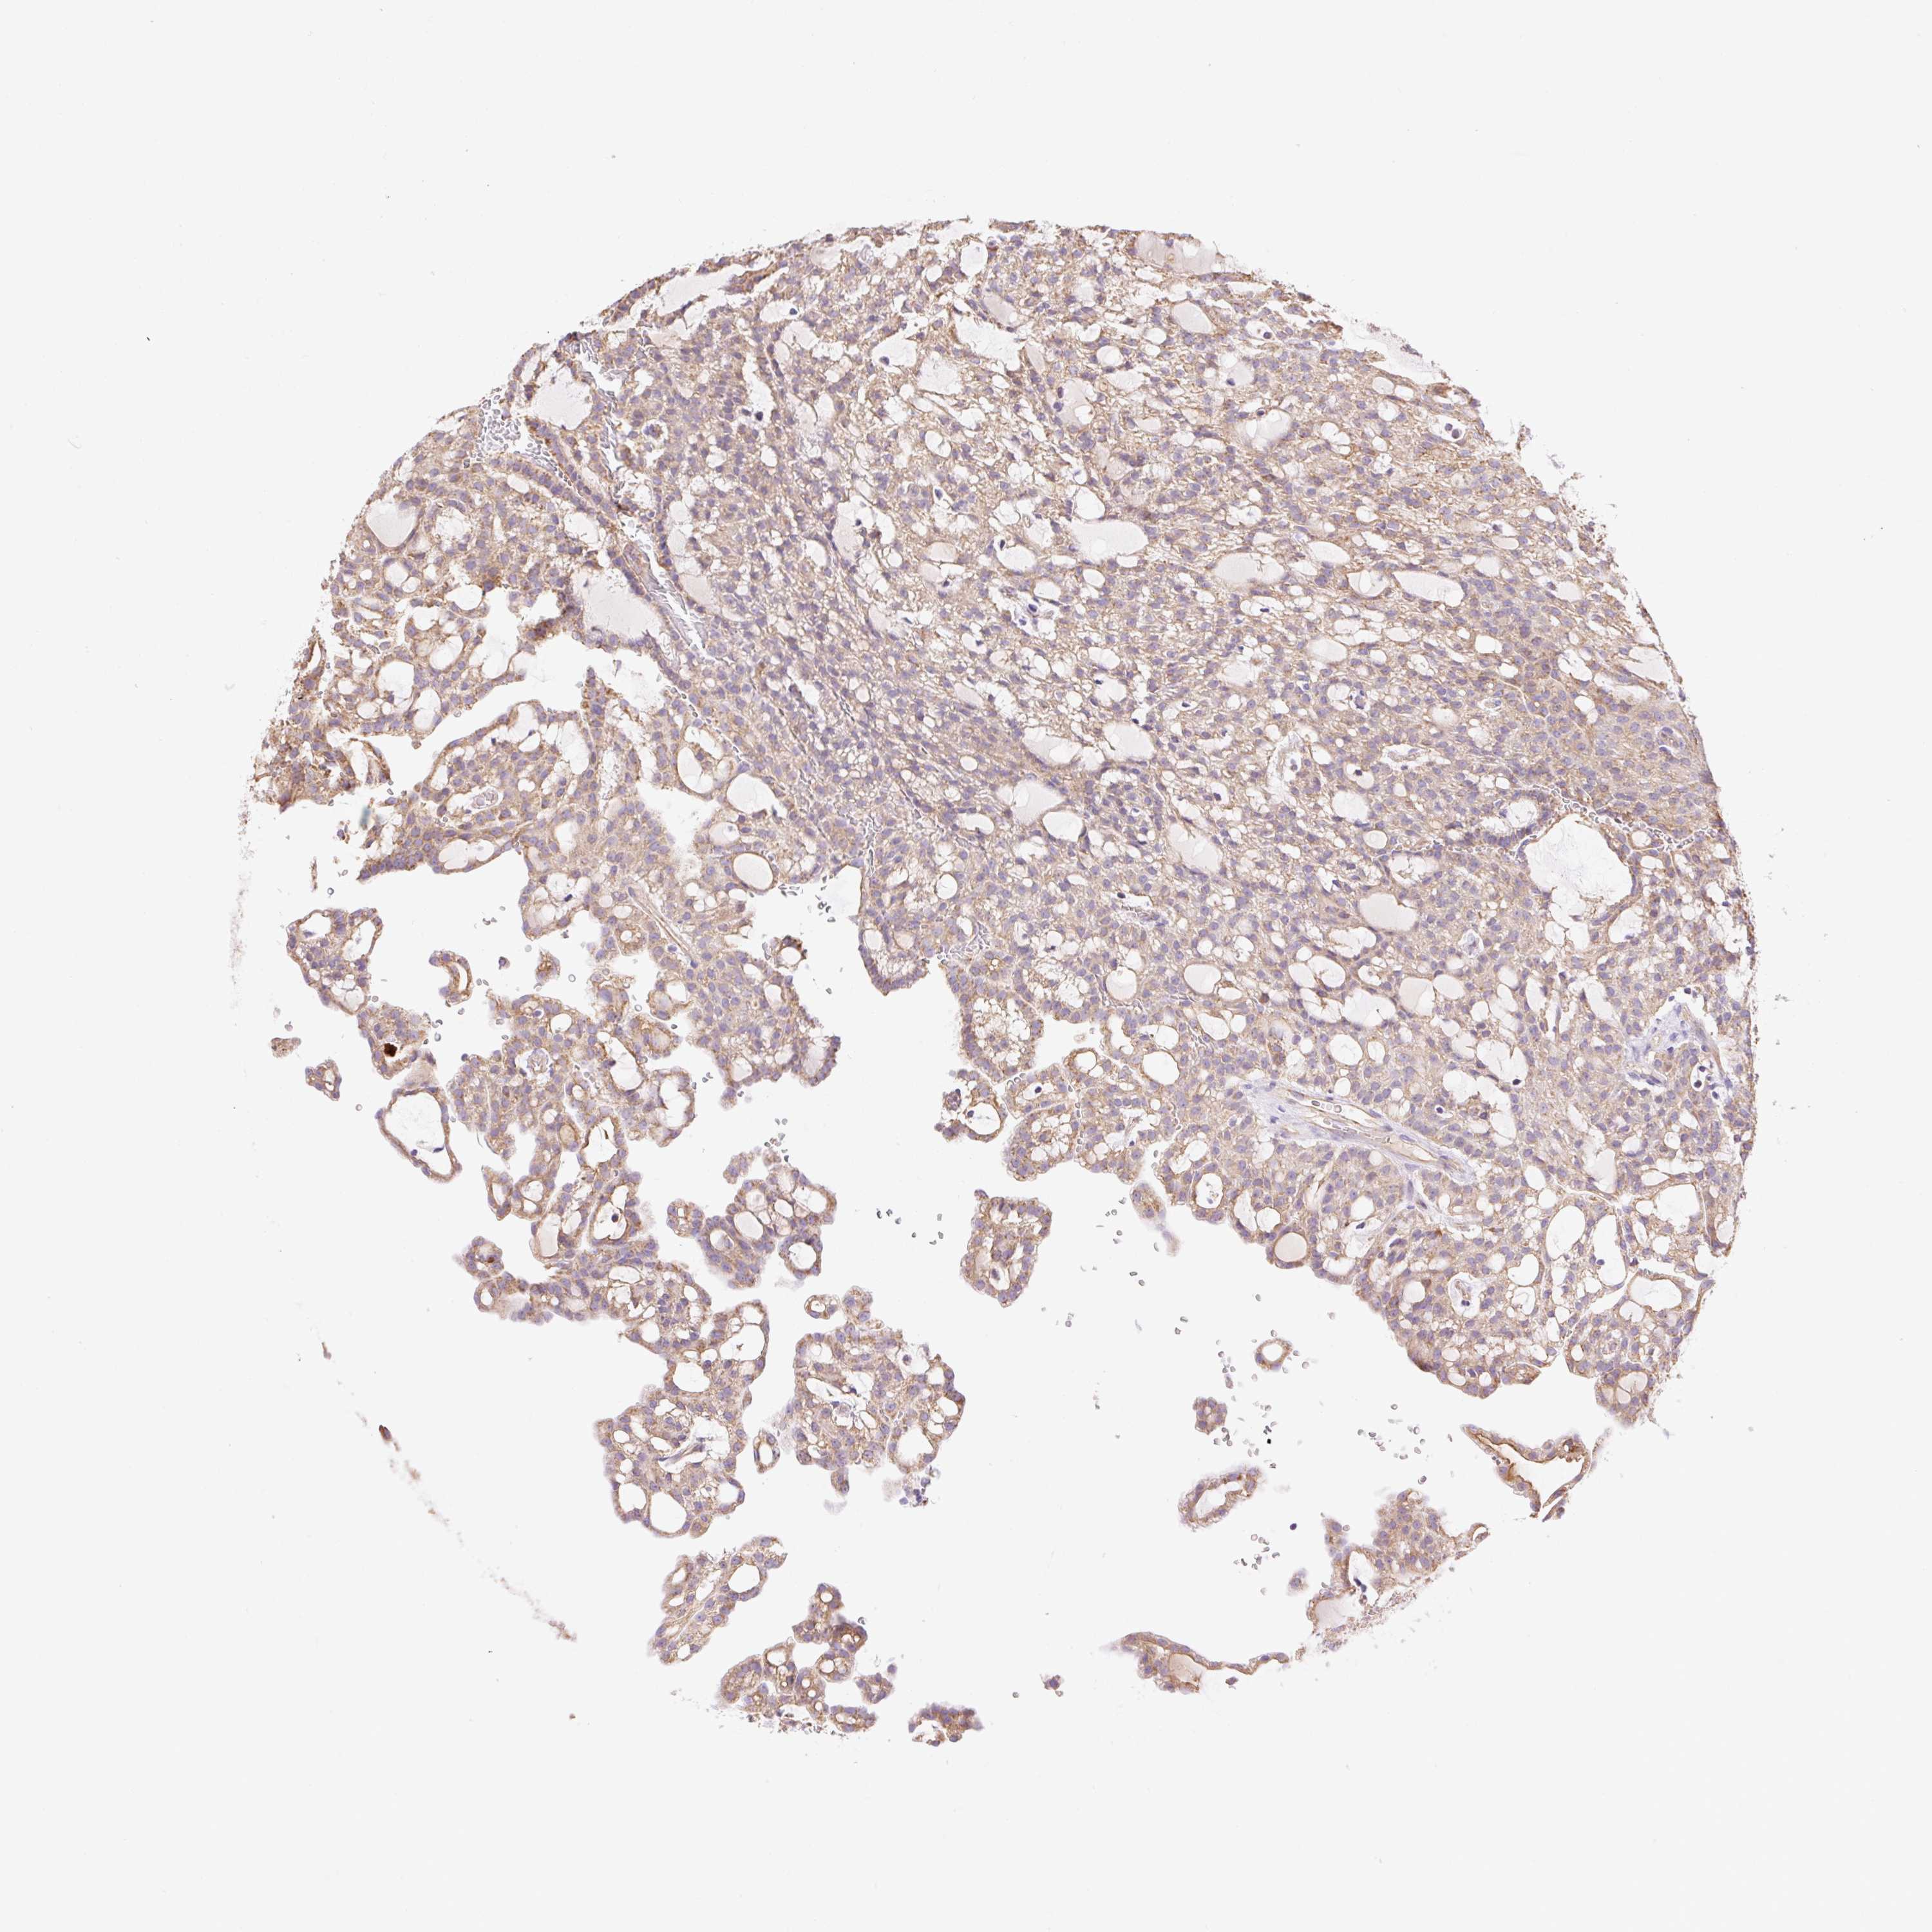

KIDNEY RENAL CLEAR CELL CARCINOMA (VALIDATION) - Interactive survival scatter ploti

The Survival Scatter plot shows the clinical status (i.e. dead or alive) for all individuals in the patient cohort, based on the same data that underlies the corresponding Kaplan-Meier plots. Patients that are alive at last time for follow-up are shown in blue and patients who have died during the study are shown in red.

The x-axis shows the expression levels (FPKM) of the investigated gene in the tumor tissue at the time of diagnosis. The y-axis shows the follow-up time after diagnosis (years). Both axes are complimented with kernel density curves demonstrating the data density over the axes. The top density plot shows the expression levels (FPKM) distribution among dead (red) and alive patients (blue). The right density plot shows the data density of the survived years of dead patients with high and low expression levels respectively, stratified using the cutoff indicated by the vertical dashed line through the Survival Scatter plot. This cutoff is automatically defined based on the FPKM cutoff that minimizes the p-score. The cutoff can be changed by dragging the vertical line or by entering a cutoff value in the square labeled "Current cut-off".

Under the Survival Scatter plot the p-score landscape (black curve; left axis) is shown together with dead median separation (red curve; right axis). Dead median separation is the difference in median mRNA expression between patients who have died with high and low expression, respectively. It is calculated as follows: median FPKM expression of dead patients with high expression - median FPKM expression of dead patients with low expression. This is intended to aid the user in visually exploring custom cutoffs and the associated p-scores and dead median separation.

Individual patient data is displayed and can be filtered by clicking on one or more of the category buttons on the top of the page. Categories describing expression level and patient information include: high, low, alive, dead, female, male and tumor stages. The scale of the x-axis can be toggled between linear and log-scale by clicking on the "x log" button. Mouse-over function shows TCGA ID, patient information and mRNA expression (FPKM) for each patient.

& Survival analysisi

Kaplan-Meier plots summarize results from analysis of correlation between mRNA expression level and patient survival. Patients were divided based on level of expression into one of the two groups "low" (under cut off) or "high" (over cut off). X-axis shows time for survival (years) and y-axis shows the probability of survival, where 1.0 corresponds to 100 percent.

ESAM is validated prognostic, high expression is favorable in Kidney Renal Clear Cell Carcinoma (validation)

Best expression cut offi

Based on the FPKM value of each gene, patients were classified into two groups and association between prognosis (survival) and gene expression (FPKM) was examined. The best expression cut-off refers the FPKM value that yields maximal difference with regard to survival between the two groups at the lowest log-rank P-value. Best expression cut-off was selected based on survival analysis .

When clicking on this number, the vertical dashed line indicating cut-off, the interactive survival plot, and the Kaplan-Meier curve will be adjusted to show results based on the best expression cut-off.

: 35.23

P scorei

Log-rank P value for Kaplan-Meier plot showing results from analysis of correlation between mRNA expression level and patient survival.

N/A

5-year survival highi

5-year survival for patients with higher expression than the expression cutoff.

For melanoma and glioma, 3-year survival is shown.

5-year survival lowi

5-year survival for patients with lower expression than the expression cutoff.

TCGA RNA samplesi

RNA-seq data is reported as average FPKM (number Fragments Per Kilobase of exon per Million reads), generated by the The Cancer Genome Atlas (TCGA) .

Normal distribution across the dataset is visualized with box plots, shown as median and 25th and 75th percentiles. Points are displayed as outliers if they are above or below 1.5 times the interquartile range. FPKM values of the individual samples are presented next to the box plot.

Average pTPM 85.0

Number of samples 100